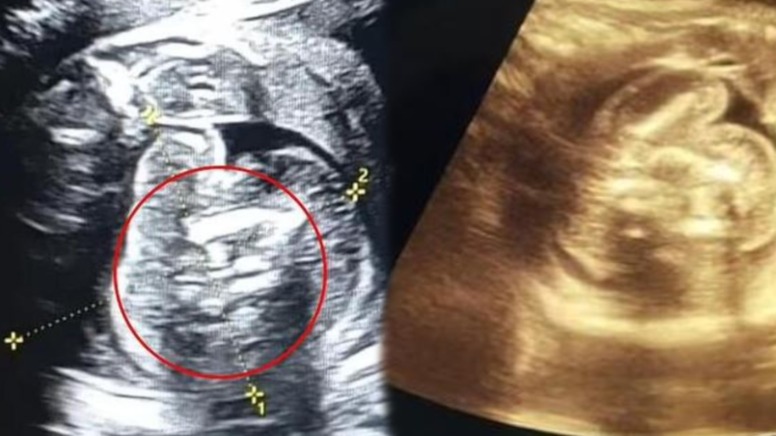

Hindistanda hamilə qadının körpəsinin qarnında iki döl olduğu üzə çıxıb.

7News.Az xarici mediaya istinadən xəbər verir ki, körpənin içində böyüməsini əngəlləyən həmin döl əməliyyatla çıxarılıb.

Əməliyyatdan sonra oğlunu dünyaya gətirən qadının da, körpəsinin də səhhətinin yaxşı olduğu bildirilib.

Baş verənlərin normal olmadığını bildirən həkim bunun dünyada ən nadir hallardan biri olduğunu deyib.